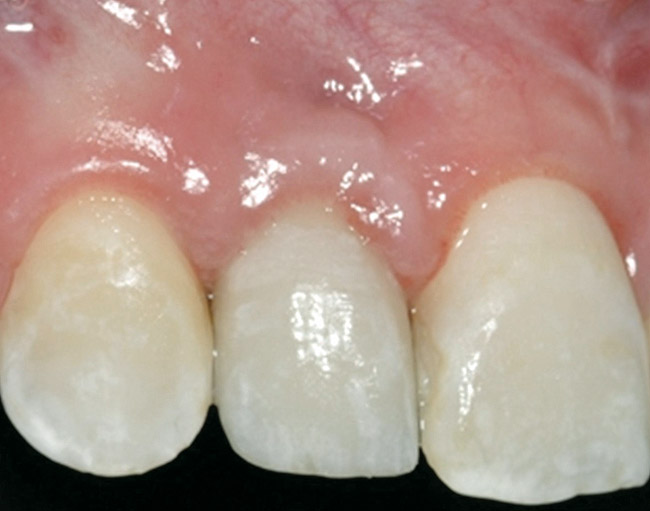

Figure 2  Congenitally missing maxillary right lateral incisor.

Figure 2

Figure 6  Facial and palatal alveolar ridge width deficiency.

Figure 6

A 16-year-old female patient with a congenitally missing maxillary right lateral incisor was referred for an implant-supported crown. Clinical and CBCT evaluation revealed both a facial and palatal bony width deficiency (Figure 2 and Figure 3). The treatment plan included the use of titanium mesh and rhBMP-2/ACS (INFUSE® Bone Graft) along with mineralized allograft (MinerOss®, BioHorizons, www.BioHorizons.com) for bony augmentation (Figure 4 and Figure 5). After 7 months, the graft was found to be well incorporated and allowed for placement of a 3.8-mm x 10.5-mm diameter root form implant that was restored 3 months later (Figure 6, Figure 7, Figure 8, Figure 9 and Figure 10).